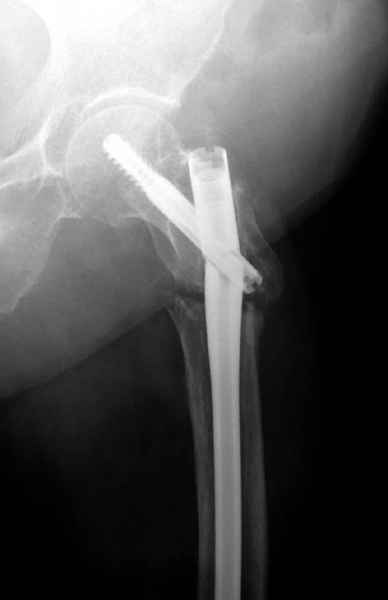

77 летняя больная направлена в нашу клинику на дальнейшее лечение. Из истории, травму получила в сентябре 2007 года и по поводу перелома шейки бедра больная была проперирована тремя каннюлированными шурупами с явным нарушением технологии установки шурупов. Внизу вместо одного шурупа имеется два, что привело к стрессу латерального кортекса. Через месяц по поводу ятрогенного подвертельного перелома сделана фиксация длинной Гамма 3. Установлен без проксимальной блокировки? (set screw). В данный момент имеется несостоятельность конструкции и ложный сустав. Передвигается с помошью костылей, конечность укорочена на 2 см. Какие будут рекомендации?Djoldas Kuldjanov, MDDepartment of Orthopedic SurgerySt. Louis University Medical Center

Видимо, проблем тут две: во-1-х, центральный отломок был оставлен в варусно-сгибательной установке, во-2-х, не динамизировали вовремя.

Нижние винты хотели сломаться, но, увы, один не сломался, и тогда сломался гвоздь. Хотя и при динамизации в таком положении отломков

могло не срастись.